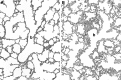

Much of the progress in improved neonatal care, particularly management of underdeveloped preterm lungs, has been aided by investigations of multiple animal models, including the neonatal baboon (Papio species). In this article we highlight how the preterm baboon model at both 140 and 125 days gestation (term equivalent 185 days) has advanced our understanding and management of the immature human infant with neonatal lung disease. Not only is the 125-day baboon model extremely relevant to the condition of bronchopulmonary dysplasia but there are also critical neurodevelopmental and other end-organ pathological features associated with this model not fully discussed in this limited forum. We also describe efforts to incorporate perinatal infection into these preterm models, both fetal and neonatal, and particularly associated with Ureaplasma/Mycoplasma organisms. Efforts to rekindle the preterm primate model for future evaluations of therapies such as stem cell replacement, early lung recruitment interventions coupled with noninvasive surfactant and high-frequency nasal ventilation, and surfactant therapy coupled with antioxidant or anti-inflammatory medications, to name a few, should be undertaken.